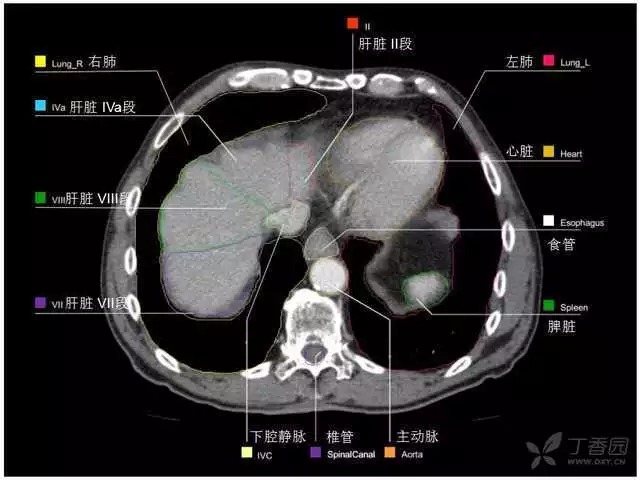

腹部肝脏高清CT断层的图谱

全腹部高清CT图谱,淋巴结彩色图谱,血管解剖图谱大汇总!

超声肝脏分叶及分段

肝脏分段和基本解剖学标志